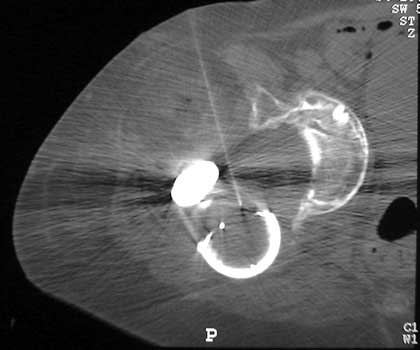

Dislocated femoral component and acetabular cup in grossly

loose arthroplasty. CT guided aspiration to rule out infection.